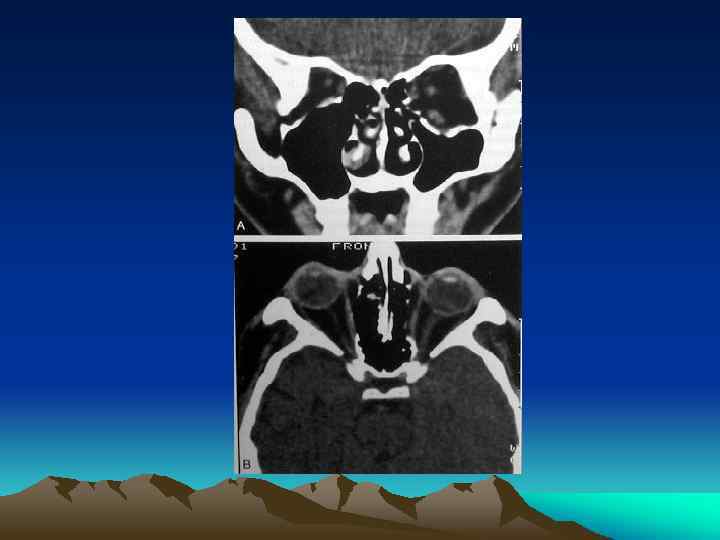

Facial Plain Films Ø Largely been replaced by computer tomography (except for the mandible) Plain Film Mandible Series and Panorex Computed Tomography (CT) Ø Most informative radiographic exam fro head and neck Trauma Ø Axial and coronal facial CT with bone and soft tissue window, 2 -3 mm sections

ORBITAL FRACTURES

INTRODUCTION Ø Ø Ø Orbital Bones Optic Canal& Orbital Fissures Contents Sign& Symptoms

TYPES Ø Pure Ø Impure

Management Ø Indication for Surgical Intervention Ø Contraindications for Surgical Intervention: hyphema, retinal tear, globe perforation, only seeing eye sinusitis, frozen globe Ø Ophthalmological Evaluation Ø Timing : 1 week Ø Technique